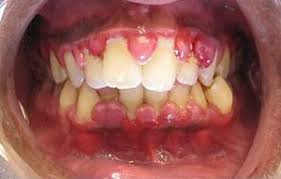

IMPORTANCIA DE LA GINGIVITIS

De la periodontitis, periodontosis, de la dentición difícil, de la formación de bolsas en encía, de la osteitis, etc., en el marco de un suceso focal dentógeno. Al respecto hay que decir lo siguiente:

La efectividad focal de estos cuadros clìnicos se basa primero en los mismos procesos inflamatorios crònicos y segundo en la reaccionabilidad vegetativa de la gigiva. Esta última "ratio" no se conocìa hasta el momento y sòlo ha podido ser aclarada gracias a las ùltimas investigaciones histològicas, electrónico-microscópicas e histo-químicas hechas por PLENK junior y RAAB (1969 1970) en nervios de la gingiva humana. Hemos comprobado allì por primera vez en la historia de la odontología científica la existencia de nervios adrenergos y autónomos (en la encia) lo que permite entender correlaciones funcionales de la misma con todo el organismo y a las que les faltaba el substrato morfològico.

La importancia clínica de este hallazgo se publicó por primera vez en 1970 (RAAB). La comprobación de que sí existen nervios vegetativos en la gingica es apropiada para explicar la hasta ahora oscurísima patofisiología de efectos a distancia "lanzados desde la gingiva" hacia todo el organismo y viceversa daños que le vienen a la gingiva proveniente de la mas variada y general gama de insultos patológicos de tipo tanto físico como psíquico (RAAB 1961). En la Universidad tenemos ya apabullantes estadísticas que le sirven de ejemplo a todo lo que estamos exponiendo.

El internista alemán M.L.Veil (1939) describió que en la mayoría de los casos con periodontosis las amigdalas se hallaban afectadas, o viceversa que una periodontosis severa y fétida solo lograba curarse después de una amigdalectomía. Se sabe además de casos en que existe una gingivitis crónica o aguda, pueden aparecer simultáneamente afecciones de caracter reumático en varias articulaciones, o molestias a distancia circunscritas a órganos. Este caso se da preferentemente en aquellos lugares del cuerpo cuya estructura heredada presenta constitucionalmente una clara debilidad de su sistema o también alrededor de sitios que sufrieron enfermedades años atrás. Sucede lo mismo con áreas cuya sobrecarga tisular es evidente por ejemplo: allí donde la estática del esqueleto está alterada. Todos estos factores crean en el cuerpo puntos de resistencia menor, mejor dicho puntos de reacción mayor, de tal modo que es allí donde anidan en primera linea irritaciones e interferencias.

Hasta ahora se venía culpando de todos estos sucesos focales que siempre acompañan, así como también a las alteraciones osteíticas. Sabemos que bajo la influencia de una situación hormonal de stress permanente como la pubertad, el climaterio y el embarazo o también un schock psíquico, como por ej: situaciones conflictivas en el trabajo y en la familia, puede presentarse una gingivitis sin que para ello podamos encontrar la culpabilidad de algún factor local. Las interpretaciones dadas a estos hechos reales no lograron satisfacernos núnca. Según nuestros conocimientos actuales sobre la morfología de la gingiva humana salta a la vista la explicación siguiente: La existencia de fibras vegetativas nerviosas de tipo adrenergico y autónomo en la encía humana, cosa hasta ahora desconocida, comprueba sin lugar a dudas que toda la estructura de sostenimiento y soporte del diente junto a su tejido conectivo elástico que le garantiza su función orgánica de cohexión y fortaleza, se somete a las regulaciones vegetativas de todo el organismo, a través de la interconexión que les facilita el tejido conectivo blando, rico en células y entretejido en toda la estructura elastica en unión con las citadas fibras nerviosas vegetativas y autónomas.